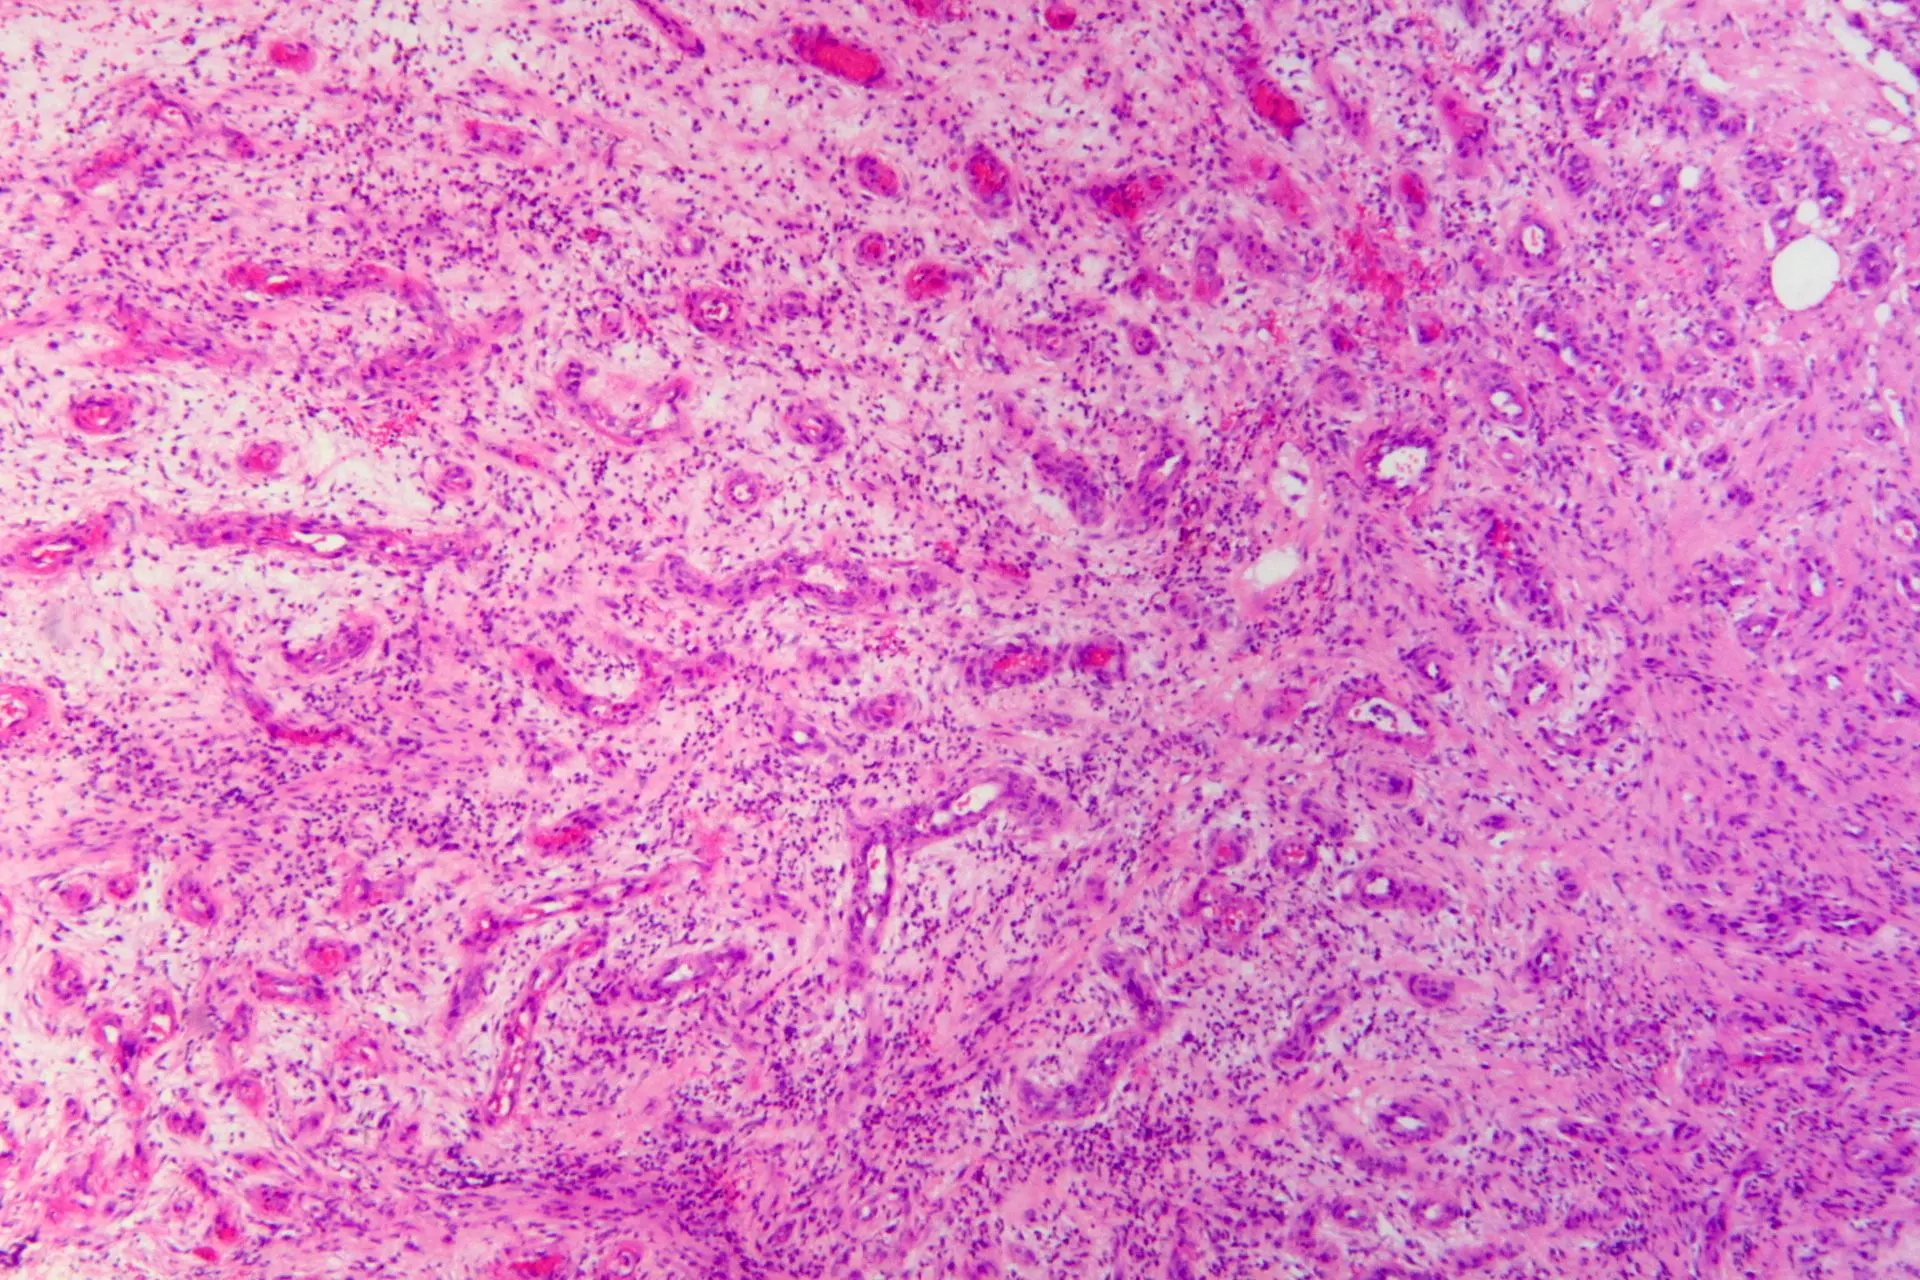

Histology of granulation tissue can be seen in the image below:

Image - The histology of granulation tissue in an infected wound. There are many blood vessels and immune cells.

The formation of granulation tissue is part of the process of organisation. Granulation tissue fills in the gap that is initially left by the damage to tissue. Angiogenesis (formation of new blood vessels) occurs within the granulation tissue, and the new capillaries provide oxygen, nutrients and cells required to repair the damage.